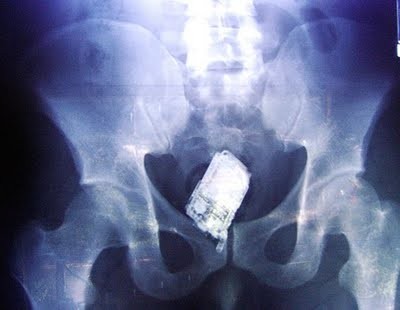

Одним из лидеров недели в Twitter стал хештег #WeirdThingsToPutUpYourAss (Странные штуки, которые суют в задницу). Проктологи со всего мира поделились рентгеновскими снимками содержимого анусов своих пациентов. Выяснилось, что огурец - еще не самое удивительно, что можно обнаружить там, где не светит солнце.